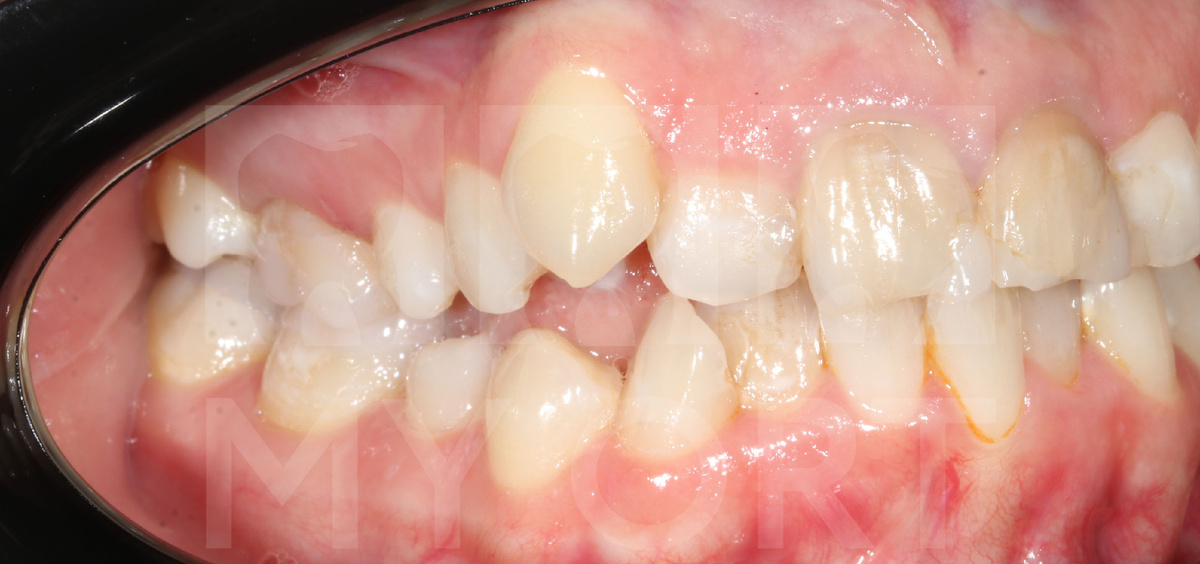

Пациентка обратилась ко мне с выраженными болями в области височно-нижнечелюстного сустава. Она жаловалась на дискомфорт при жевании, болезненные ощущения при движении нижней челюстью и ощущение усталости мышц. Кроме этого, ее беспокоила скученность зубов и неэстетичное положение верхнего правого клыка.

Также была обнаружена значительная скученность зубов, отсутствие места для прорезывания 13-го зуба и ранее перенесенная дисфункция височно-нижнечелюстного сустава, которая требует строгого функционального подхода.